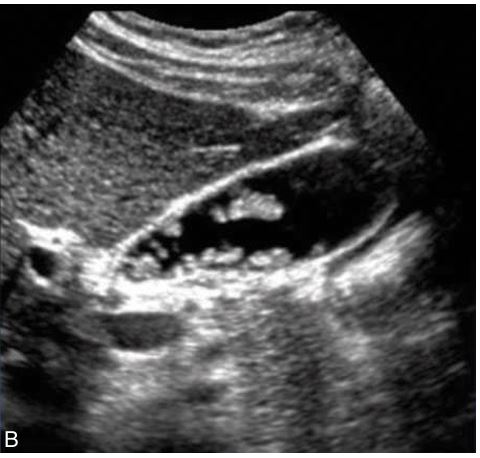

# 1 Pt. c/o RUQ pain, this image looked the same in both supine and LLD positions. Name the pathology

Cholesterolosis showing multiple cholesterol polyps

The lesion remains immobile

No Acoustic Shadow

Artifact: comet tail

Adenomyomatosis

HINT: NO FEVER

Cholelithiasis

sludge

Adenomyomatosis

artifact: comet tail

porcelain gallbladder

Adenocarcinoma

the most common pseudotumor of the gallbladder

Cholesterol polyps

what are these pics showing?

Cholesterol polyps

What is the most common benign tumor of the gallbladder?

Cholesterol polyps